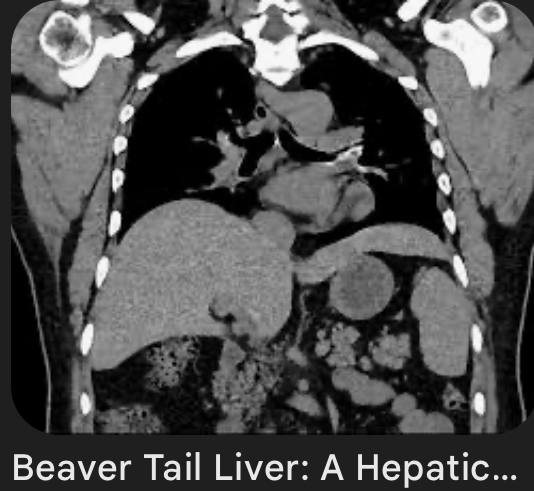

40 лет.

Думаю, что рак в хвосте панкреас, с вот такими метастазами в печень.

Ну, или и в панкреас тоже метастаз, хотя, других опухолей в животе не обнаруживается.